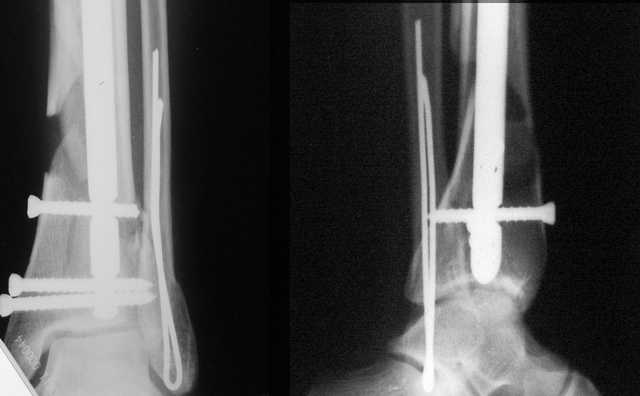

Да и нет! Зависит от перелома и способа остеосинтеза. А результат? (01)

А.Миронов

Кликните для загрузки файла 01.jpg

Мы же говорили о проксимальном плече. При переломе tibia, конечно, речи о двух Y-спицах нет. Еще раз о них - пружинящая подвижность без "срезающих" перемещений фрагментов - дополнительный стимул к образованию периостальной мозоли.

А в данном случае - у нас был бы применен locked nail с еще меньшими дырочками на коже и с возможностью полной нагрузки немедленно после операции. Какие тут аргументы в пользу выбора пластины, а не интрамедуллярного гвоздя?